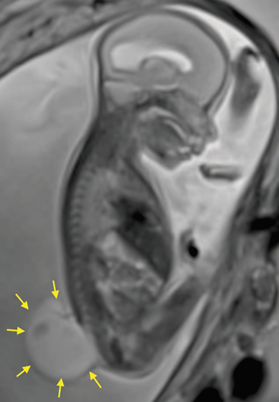

Primigesta de 27 años de edad y 25 semanas de edad gestacional, con el diagnóstico de feto con espina bifida abierta (MMC), ventriculomegalia y síndrome de Arnold Chiari II, programada para corrección intrautero de MMC. En la Figura 1, se puede apreciar la RMN donde se evidencia la extensa lesión vertebral fetal. Paciente sin antecedentes personales de relevancia, a la evaluación del estado físico: ASA II, peso: 84 Kg; talla: 169 cm; IMC: 29; presión arterial (PA): 110/70 mmHg; frecuencia cardiaca (FC): 74/min; sin predictores de vía aérea difícil, ni hallazgos patológicos cardiopulmonares. Exámenes de laboratorio: Hemoglobina: 12.3 g/dl., Tiempo de Protrombina: 11.5 segundos, Tiempo parcial de Tromboplastina: 26.2 segundos, Fibrinógeno: 310 mg/dl., Recuento de plaquetas: 234000/mm3. Se explica a la paciente y al esposo las técnicas anestésicas y luego de mencionarle los riesgos y beneficios de éstas, se considera la colocación de catéter epidural para manejo de dolor postoperatorio, seguido de anestesia general endovenosa, previo consentimiento firmado.